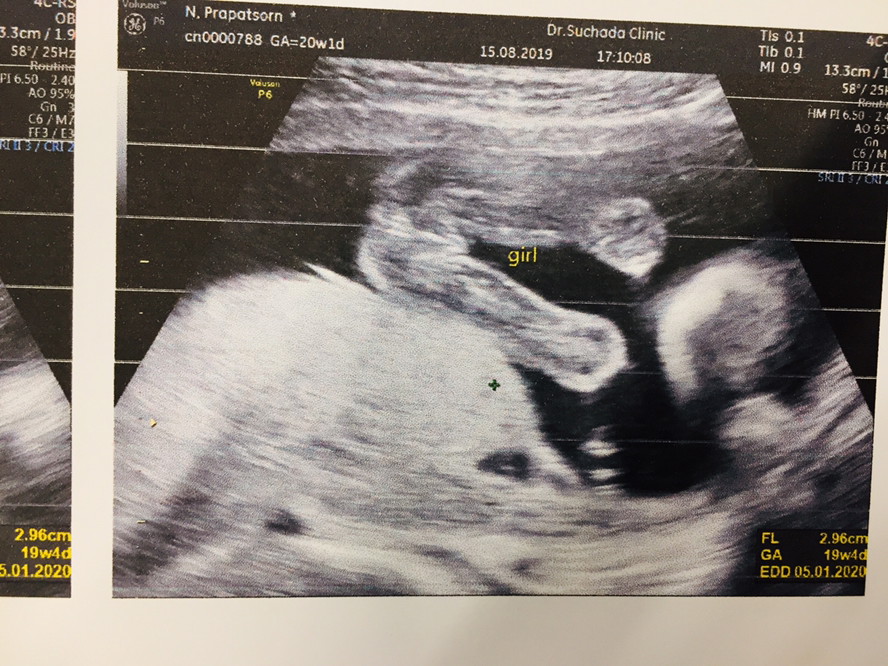

4 เดือน 1 สัปดาห์จ้า น้อง ผญ คะ

5 เดือน 1 วัน ลูกสาวค่ะ 👧🏻